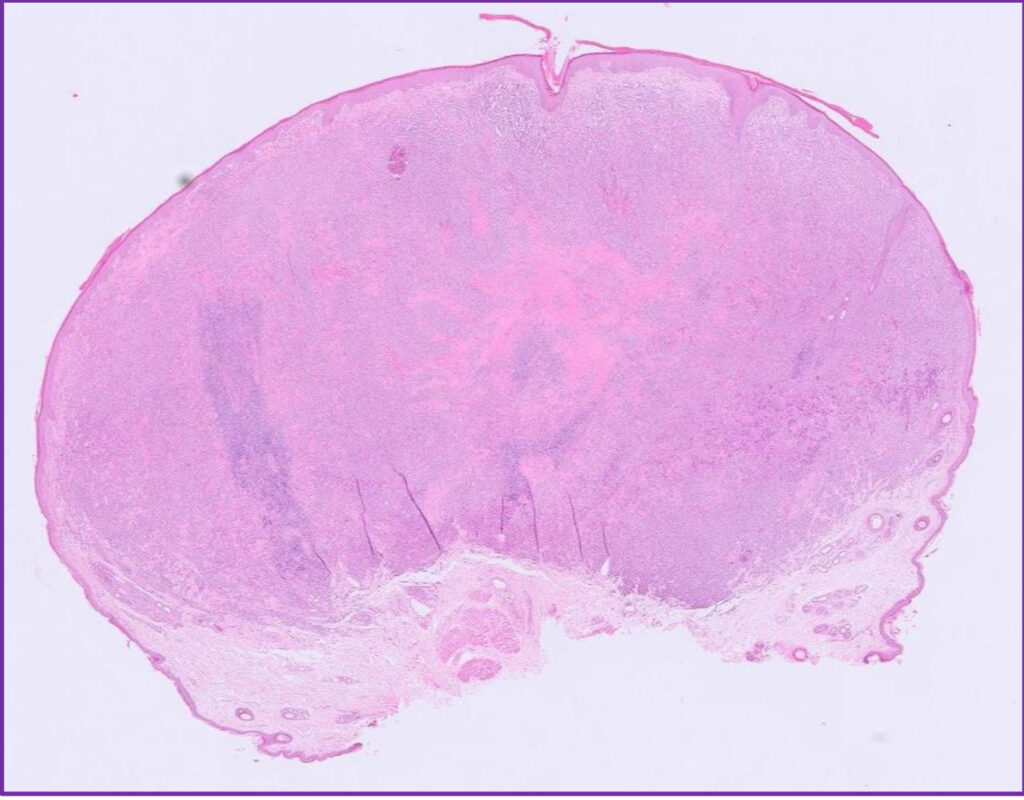

Fig 4. Canine cutaneous histiocytoma.